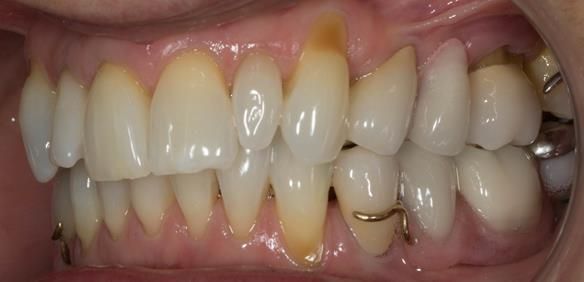

This newsletter describes in step by step detail Angela's transition through immediate partial dentures to crown supported definitive metal based dentures.

This 58 year old woman was referred to me by her general dental practitoner for treatment.

- Generalised Periodontitis; Stage 4, Grade C, Currently Unstable. Risk Factors: Type 1 diabetes. 16, 17 - hopeless prognosis. 14, 24, 26, 27, 34, 37, 44 - guarded prognosis

- Poor marginal fit and poor appearance of crowns and bridgework

- Yellowing teeth

The clinical situation and treatment process is shown in detail below with photographs. I (Finlay Sutton) provided the clinical work and Rowan Garstang provided the technical work.